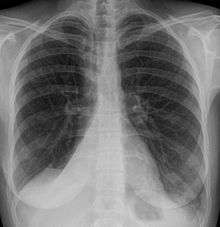

Atelectasis is the collapse or closure of a lung resulting in reduced or absent gas exchange. It may affect part or all of a lung.[1] It is usually not bilateral. It is a condition where the alveoli are deflated down to little or no volume, as distinct from pulmonary consolidation, in which they are filled with liquid. It is often called a collapsed lung, although that term may also refer to pneumothorax.[2]

It is a very common finding in chest x-rays and other radiological studies. It may be caused by normal exhalation or by several medical conditions. Although frequently described as a collapse of lung tissue, atelectasis is not synonymous with a pneumothorax, which is a more specific condition that features atelectasis. Acute atelectasis may occur as a post-operative complication or as a result of surfactant deficiency. In premature neonates, this leads to infant respiratory distress syndrome.